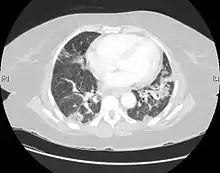

![]() | |

| CT scan of a patient with UIP. There is interstitial thickening, architectural distortion, honeycombing and bronchiectasis. | |

UIP may be diagnosed by a radiologist using computed tomography (CT) scan of the chest, or by a pathologist using tissue obtained by a lung biopsy.

Radiology

Radiologically, the main feature required for a confident diagnosis of UIP is honeycomb change in the periphery and the lower portions (bases) of the lungs.[3]